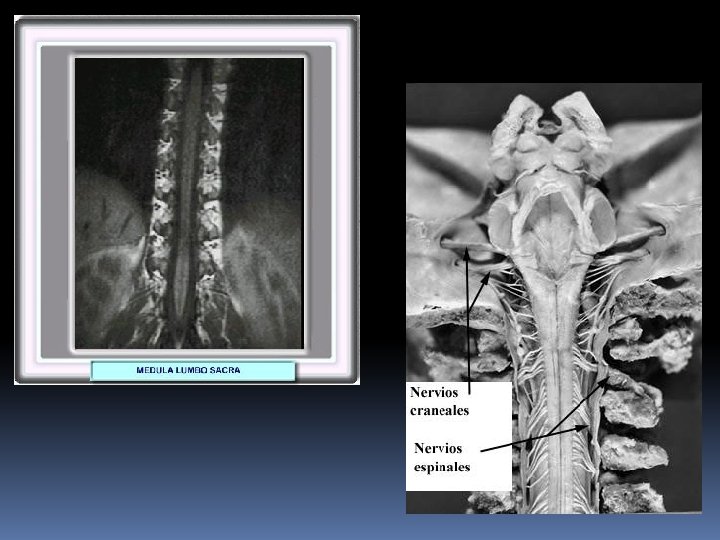

Nervios Raquídeos o Espinales: 31 pares

NERVIOS CRANEALES